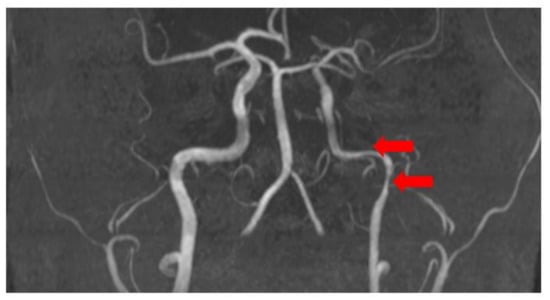

Brain magnetic resonance imaging (MRI) with magnetic resonance angiography (MRA) with intravenous contrast was performed with sequences as follows: FLAIR, MP reconstructions, T2 SE ax, DW ax, SW ax, MRA, 3D TOF, and MIP reconstructions, T2 core with fat saturation, T1 SE sag post-contrast. The radiological findings included diffusely expanded ventricles and cortical grooves, as well as segmentary stenosis in the extracranial part of the left internal carotid artery (see Figure 3).

Figure 3. Segmentary stenosis in the extracranial part of the left internal carotid artery (MRA) (red arrays).